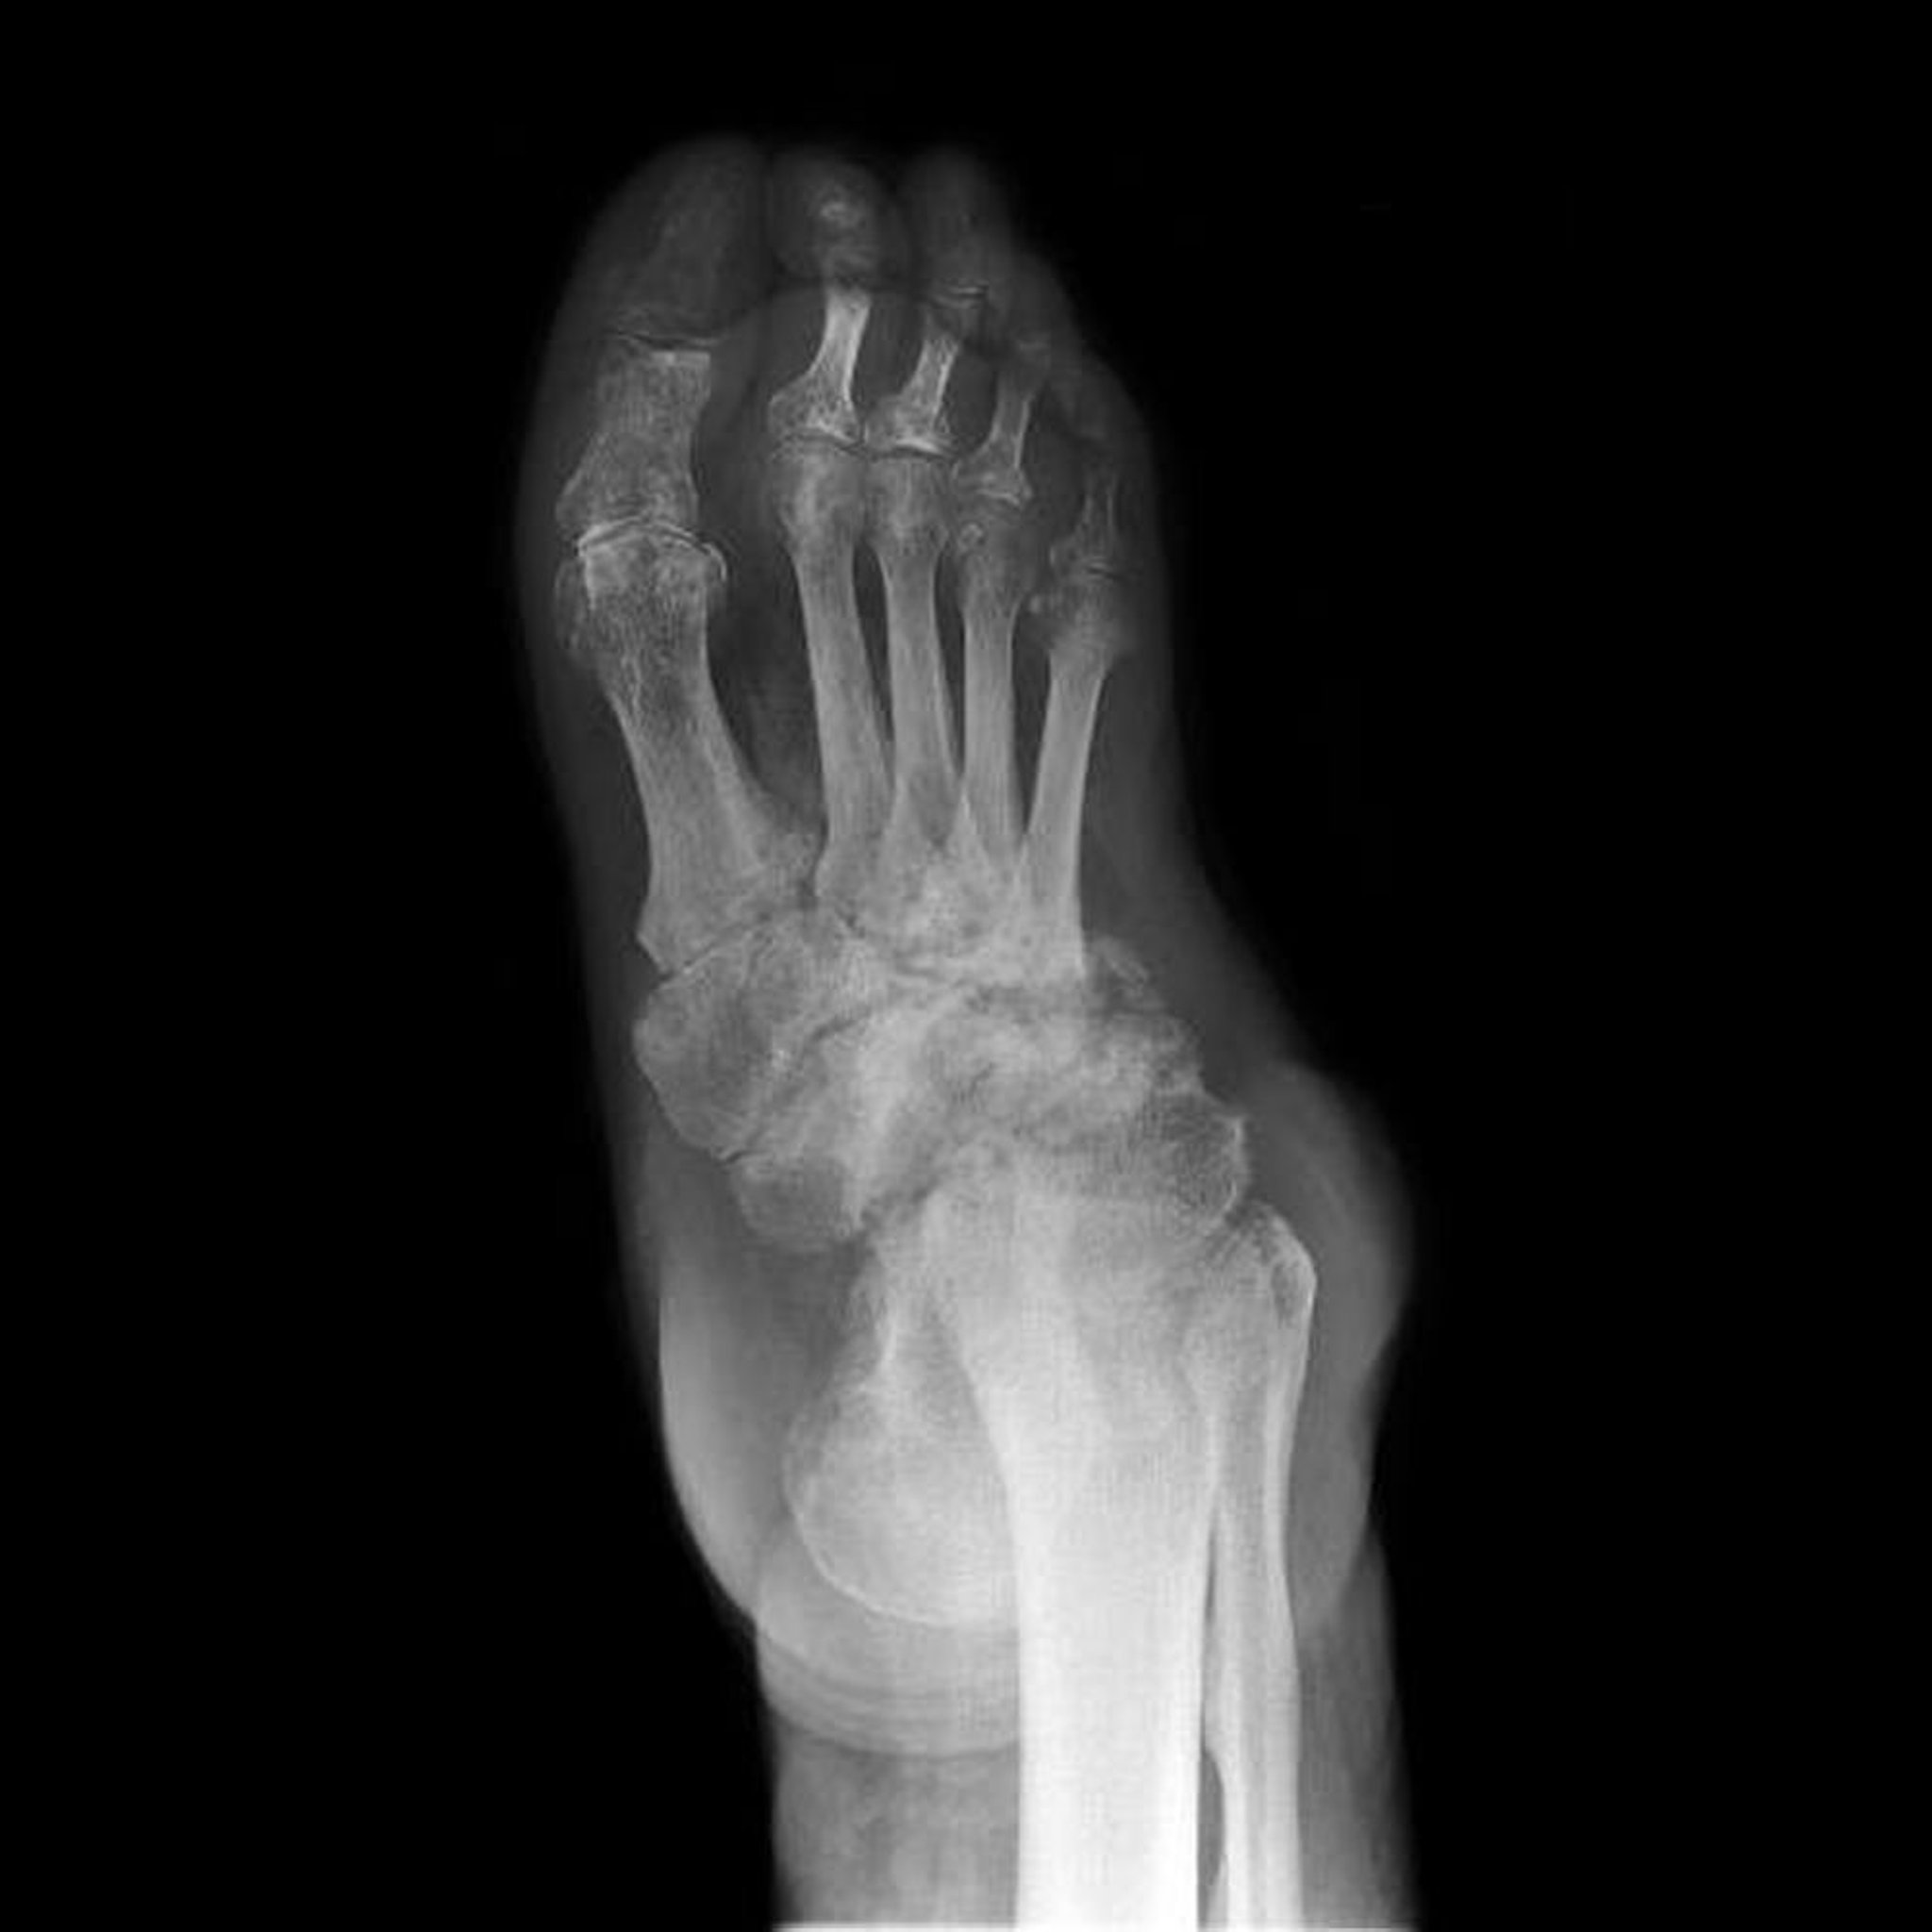

Neuropathische Arthropathie des Fußes

Diese Röntgenaufnahme zeigt eine neuropathische Arthropathie des Fußes (auch bekannt als Charcot-Fuß). Zerstörung, Deformitäten und Verlust von Gelenkräumen der Tarsalknochen sind umfangreich.